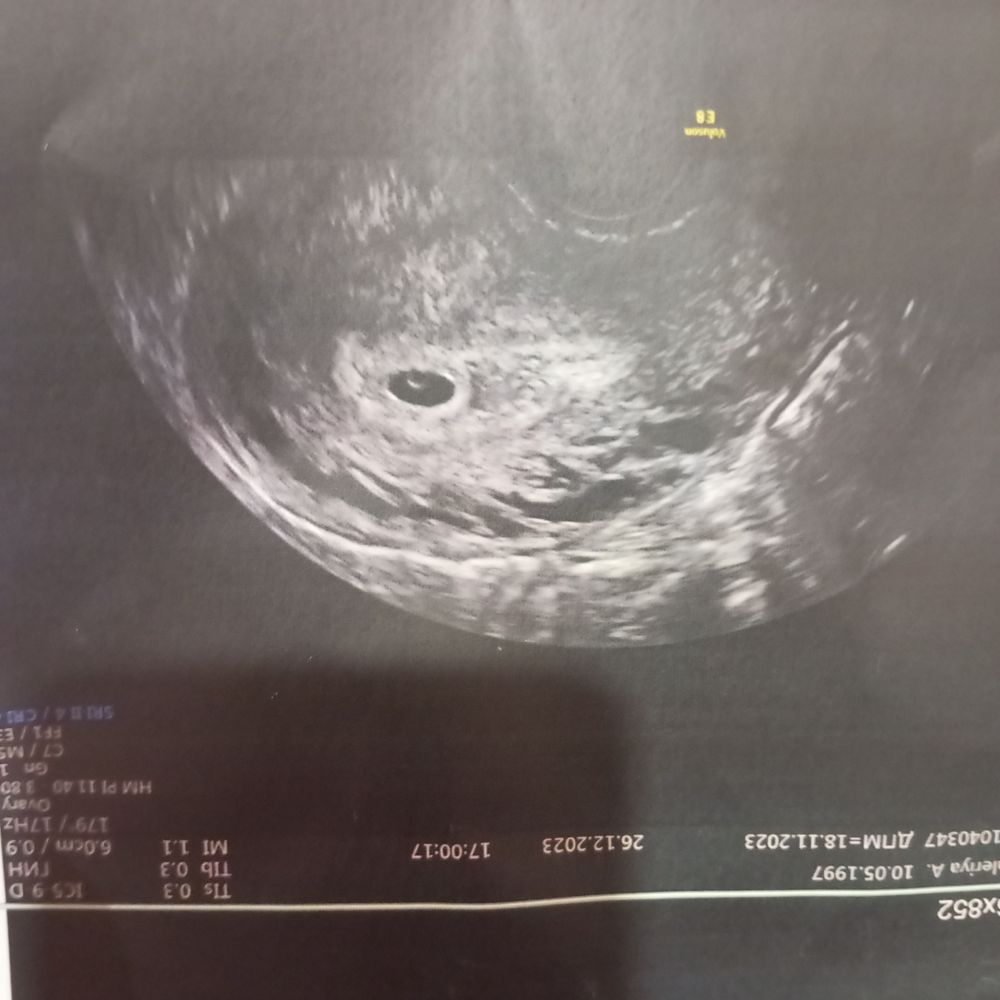

Сегодня срок 5,3 недели. Пошла на узи спустя неделю предыдущего. Эта малявочка меня поражает. Так быстро эмбриончик у меня еще не находили( всегда поздняя овуляция). А тут в 4.3 недели нашли ПЯ , а сегодня нашли жм и эмбриончик. Совсем маленький. Но нашли. Ктр всего 2.1мм. Я счастлива и теперь новый год могу встречать спокойно. 🤗все соответствует сроку